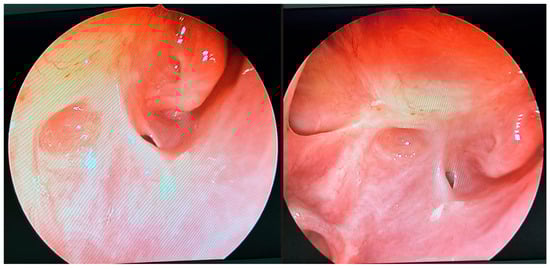

At the patient’s initial presentation at the Otolaryngology Department of the secondary hospital, the magnetic resonance imaging (MRI) of orbits revealed infiltration of the right frontal, ethmoid and maxillary sinuses, extension into the right orbit’s soft tissue and extraocular muscles with optic nerve invasion (Figure 1). The ophthalmological examination revealed central retinal artery occlusion. The treatment with ceftriaxone, vancomycin, fluconazole, mannitol and methylprednisolone was initiated. Due to clinical suspicion of mucormycosis, the patient was transferred to the University Hospital in Cracow.

Figure 1. Initial pre-operative magnetic resonance imaging. T2-weighted MRI scans of the orbits. (A)—sagittal, (B)—frontal, (C)—transverse planes. Visible infiltration of extraocular muscles and optic nerve. Inflammatory opacifications in ethmoid cells and maxillary sinus, extending into the orbital adipose tissue and extraocular muscles, causing osseous destruction of ethmoid cells.